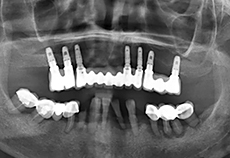

治疗过程:导板引导下下颌外科手术植入6颗种植体

治疗过程:植入6颗种植体